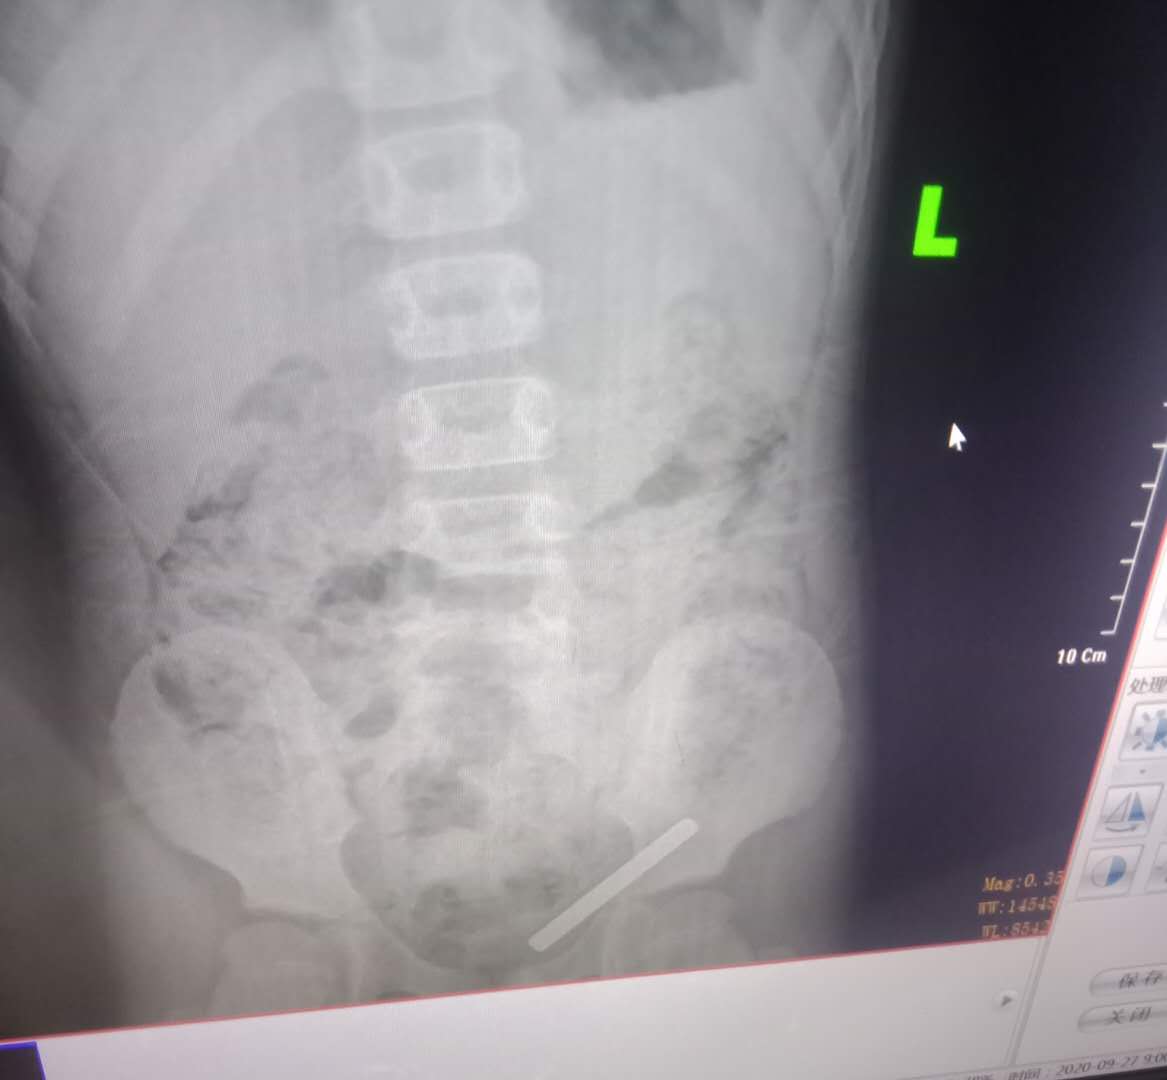

令人惊喜的是,第二天早上再去复查时,小铁棍的位置发生改变,已经移动到了肛门的旁边。

中午的时候,小铁棍终于被排了出来,看到那根明晃晃的小铁棍,我重重的舒了一口气。